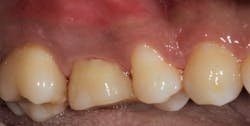

The prognosis is good for molar teeth treated with root amputation, provided case selection and treatment are performed properly. Fugazzottoreported 15-year cumulative success rates comparing molar root resection to molar implant placement, with survival rates of 96.8% for root-resected molars and 97.0% for molar implants.10 This study was done in private practice with proper oversight and case selection.Conclusion

Root amputation remains a viable treatment to save maxillary molars and can have long-term success rates equal to dental implant therapy (figures 9 and 10).Editor’s note: This article originally appeared in Perio-Implant Advisory, a chairside resource for dentists and hygienists that focuses on periodontal- and implant-related issues. Read more articles and subscribe to the newsletter.